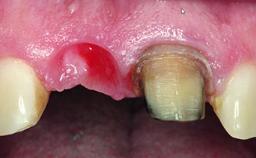

Replacement of a Compromised Upper Right Central Incisor: Hard- and Soft-tissue Augmentation, Late Placement of an RC Bone Level Implant

A 36-year-old male patient with a compromised maxillary central incisor was referred by his general dentist for consultation. The patient’s chief complaints were the gradual debonding of a temporary crown on the right central incisor and unsatisfactory esthetics due to an increasing diastema between the right central and lateral incisors. The patient reported a traumatic event some years previously, when a crown had been placed after root-canal treatment. The referring dentist wanted to provide a new crown restoration, but was concerned about the condition of the residual root. Anamnesis was negative for any other dental or periodontal pathology in the remaining dentition. The patient reported taking no medications: He was a smoker (10 to 15 cigs/day) and had realistic esthetic expectations.

Soft Tissue Anatomy Intact Defective

Bone Volume Horizontally and vertically sufficient Horizontally deficient Deficient vertically or deficient vertically AND horizontally